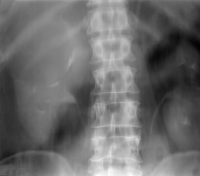

Diagnose und Behandlung von komplexen renalen Zysten bzw. unklaren Befunden umfassen eine Kombination von Sonographie, Urographie und CT (Abbildung 1). Dadurch soll eine Abgrenzung zwischen gutartigen und bösartigen Veränderungen erfolgen.